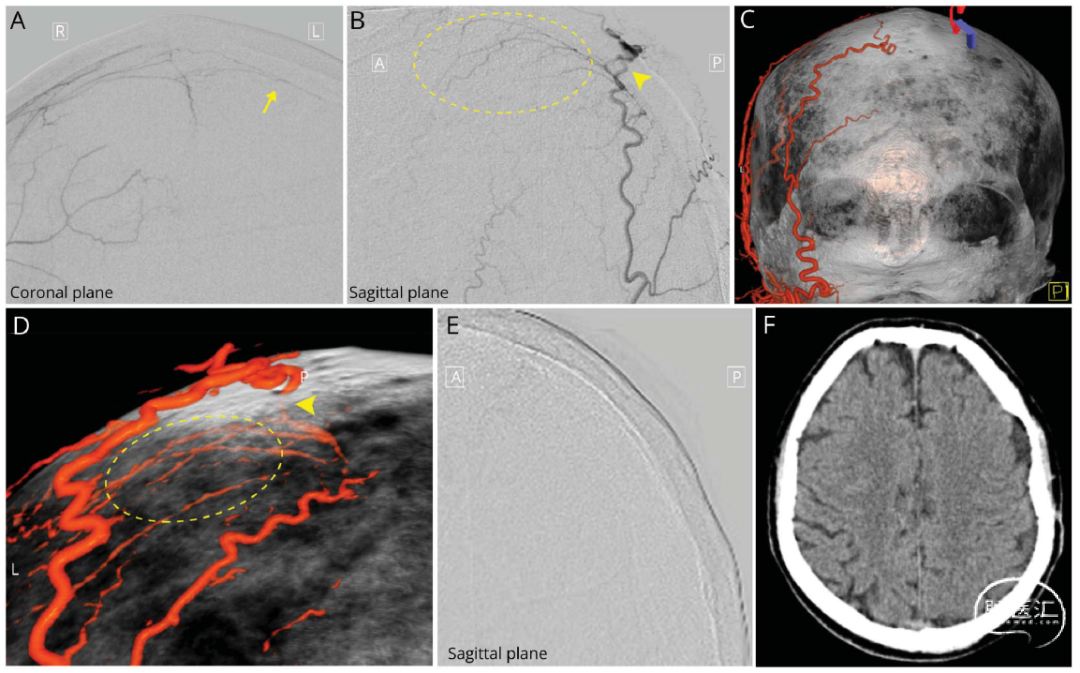

该团队报告了一例65岁左侧CSDH患者的诊疗过程。头颅MRI显示左侧血肿,但CT血管成像和7T高场强磁共振血管成像发现对侧MMA出现“反常增粗征”(图1),提示可能存在异常血供来源。DSA进一步证实,血肿包膜的血供不仅来自同侧MMA,还包括对侧MMA及同侧枕动脉分支(图2A-D)。团队进行了"血肿包膜全供血动脉栓塞",同时栓塞上述所有供血动脉,术后3个月随访显示,血肿完全吸收且未复发(图2E-F)。

图2. 栓塞术中及术后影像。(A)冠状位造影显示右侧脑膜中动脉(MMA)对血肿包膜的跨中线侧支供血(箭头)。(B)矢状位造影显示左侧枕动脉分支于顶枕区域(三角箭头)穿透颅骨形成侧枝吻合供血(圆圈内)(C和D)冠状位及矢状位双源CT重建显示左侧枕动脉穿支(三角箭头)供血。(E)栓塞后的左侧颈外动脉矢状位造影。(F)3个月后复查头颅CT显示血肿几乎完全吸收。

该病例提示血肿包膜血供多样性分布可能是单纯MMA栓塞失败的关键原因,当出现对侧MMA“反常增粗征”时,应警惕异常侧支的替代供血。通过多模影像评估识别,制定个性化方案,能够降低栓塞复发率。